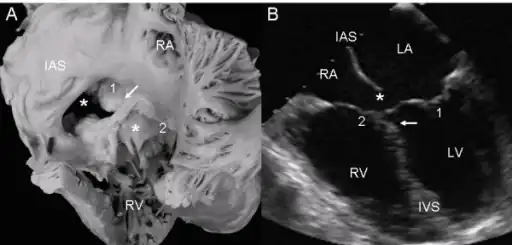

a,b)Atrioventricular septal defect with two separate atrioventricular valves. -